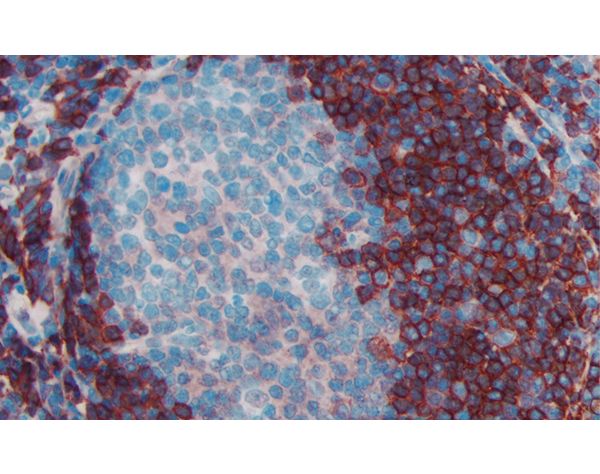

The peroxidase micropolymers of the ImmPRESS HRP polymer reagent limit steric interference and provide enhanced accessibility to the target, avoiding the disadvantages of other polymer systems that use large dextrans or other macromolecules as backbones. The result is crisp, strong staining of antibody targets, especially nuclear and membrane antigens (such as Ki67, estrogen receptor, bcl-2, CD3, CD8 and CD10) and greater sensitivity than other polymer systems.